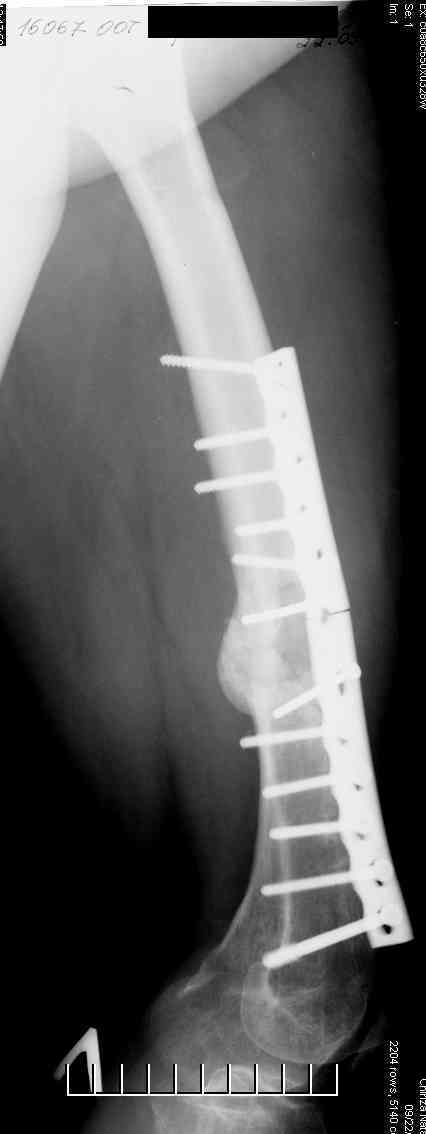

Соматически здорова. В ноябре 2004 года падение с высоты 12 м, перелом правой вертлужной впадины со смещением, неврит седалищного нерва, откр. перелом дистального отдела большеберцовой кости справа и закрытый перелом с/н/3 левого бедра. К нам поступила через 3 недели после травмы, был выполнен в 2 сессии сначала интрамедуллярный ретроградный остеосинтез бедра слева, затем остеосинтез вертлужной впадины и голеностопа справа. При остеосинтезе бедра пришлось немного приоткрыться в зоне перелома для репозиции и вообще операция затянулась часа на 2.5-3 (это один из наших первых интрамедуллярных синтезов). Через 4 месяца при нагрузке весом около 50 кг постепенно развилась варусная деформация бедра с искривлением стержня. Закрыто выпрямили под наркозом, динамизация гвоздя,но в сентябре 2005 г. согнулось бедро снова. Гвоздь удалили, остеосинтез пластиной, декортикация, пластика спонгиозой из метафиза б/берцовой кости. Динамика заживления вялая, но конструкция стояла неплохо (без признаков расшатывания), постепенно дали нагрузку - в марте 2006 года - перелом пластины - реостеосинтез пластиной, пластика гребнем подвздошной кости. На контролях (за август, т.е. 4 мес. после операции - прилагаю) динамика положительная, разрешена нагрузка до 50 кг. В начале этой недели без падения вновь появились боли в бедре - на Р-граммах - перелом пластины (снимки прилагаю). Фоном ко всему этому то, что и перелом вертлужки и дистального отдела б/б кости тоже не срастаются, хотя на голени уже дважды выполнялась костная пластика, на впадине - вторичное смещение, перелом части металлоконструкций. Исследовали гормональный фон - парат-гормон и прочие щитовидные в норме, месячные регулярно.Прошу совета по тактике дальнейшего лечения и выяснения причины тотального несращения всего сломанного.

Уважаемый Александр. Случай достаточно интересный, поскольку за 2 года,почему то ничего не срастается и все ломается. Жаль нет рентгенограмм таза и голени.Основными причинами несращения переломов бывает 1.не правильно выбранная тактика лечения, в том числе тактика оперативного лечения ( к примеру - не тот фиксатор, не того размера, неправильно установлен и т.д.)2.Девитализация костных отломков, а судя по рентгенограммам старались вы на совесть, когда открывали область перелома при интрамедуллярном остеосинтезе. Кстати, если это был не блокируемый остеосинтез, а обычный, то понятно почему стержень согнулся и нет сращения. На представленных рентгенограммах отдельные винты расположены даже с внутренней стороны, т.е. открылись вы качественно. 3.не правильно выбранная тактика лечения в п.операционном периоде или не выполнения больным данных рекомендаций. По бедру - мы бы убрали пластину и выполнили ретроградный блокируемый остеосинтез с рассверливанием. Если нет возможности, есть аппарат Илизарова. Но мороки и для вас и для больного много.

Винты с внутренней стороны кости фиксируют трансплантат, взятый из гребня подвздошной кости. Он довольно массивный и был уложен в дефект по передне-медиальной поверхности кости. тут уж пришлось действительно открываться на совесть.

В приложении рентгенограмма бедра за авгутст 2005 с согнутым гвоздем и первичные.